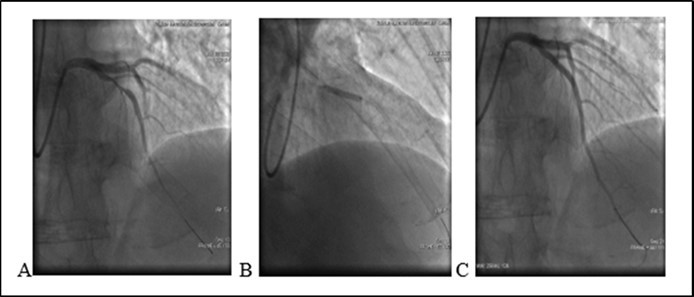

An 46-year old non-diabetic mail without history history of coronary artery disease 08.06.2020 was admitted to the cardiology department of Bokhua Memorial Cardiovascular Center ,with diagnoses of unstable angina (UA). Coronary angiography revealed 80% stenosis in medial segment of Left Anterior Descenting Artery (LAD). One bare metal stent was implanted in the stenotic segment (see Figure 1). The procedure was performed sucssesfully , without any procedure-related complications. After stent placement at hospital patient remaind simptom free. Heamodinamic parameters were stabile and he was discharged from hospital with appropriate prescription.

Figure 1.(08.06.2020) A. Medial stenosis in LAD. B. Stent implantation. C. Final result

(08.06.2020) A. Medial stenosis in LAD. B. Stent implantation. C. Final result